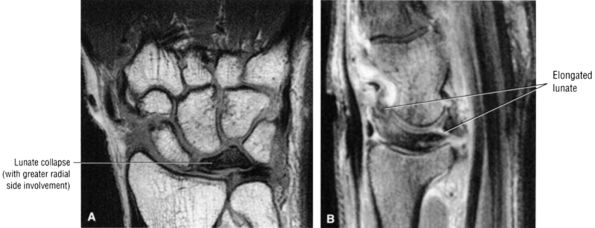

-

Pain and numbness or tingling in the median nerve distribution with increased nocturnal pain and/or burning (can be classified as mild, moderate, or severe based on electrodiagnostic data or by severity of clinical symptoms)

Involvement of the thumb, index, middle fingers, and radial half of the ring finger is most common.

Sensory findings ranging from minimal hypesthesia to complete anesthesia

Muscle atrophy and loss of function are usually late findings, although abductor pollicis brevis involvement and opponens weakness may be seen earlier (opponens atrophy is a late finding).

Positive clinical tests for nerve entrapment: